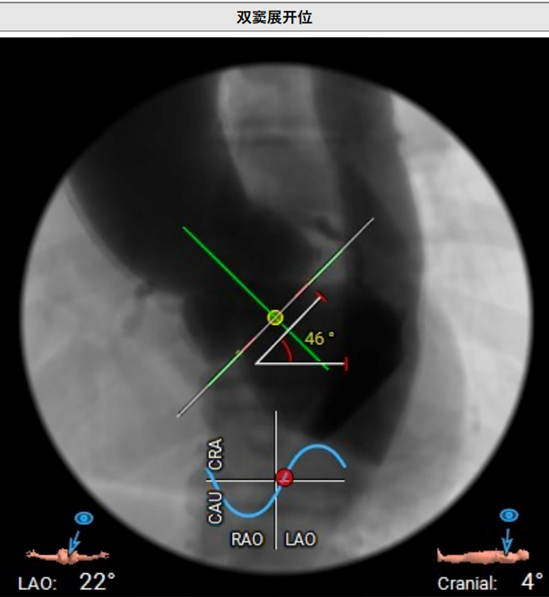

主动脉瓣环与水平面夹角46°。

血管入路评估:腹主动脉及髂总动脉可见散在钙化,右侧髂外动脉最细5.8 mm(平均径5.9 mm),左侧髂外动脉最细5.8 mm(平均径6.1 mm)。双侧股动脉分叉点较高。23#瓣膜选用22F大鞘。